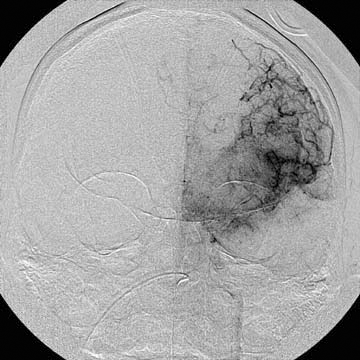

A diagnostic angiography was done during his hospitalization and yielded the following images.